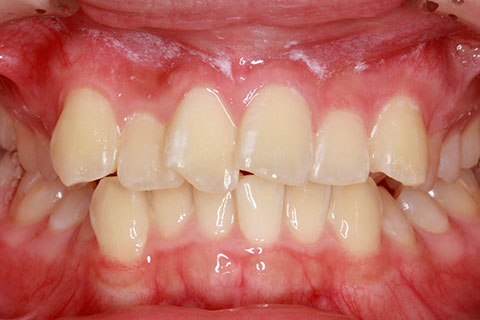

オールセラミックの症例1

上顎前歯のデコボコと色調を改善。

- 年齢・性別

- 40歳女性

- 治療期間

- 1ヶ月

- 抜歯

- なし

- 治療費

- 35.2万円

- 備考

- 前歯4本の変色歯及び歯列不正によるセラミック治療

- 治療内容

- 歯質を削除し、セラミック冠をセメント合着

- 施術の副作用(リスク)

- 知覚過敏、歯髄炎、荷重負担